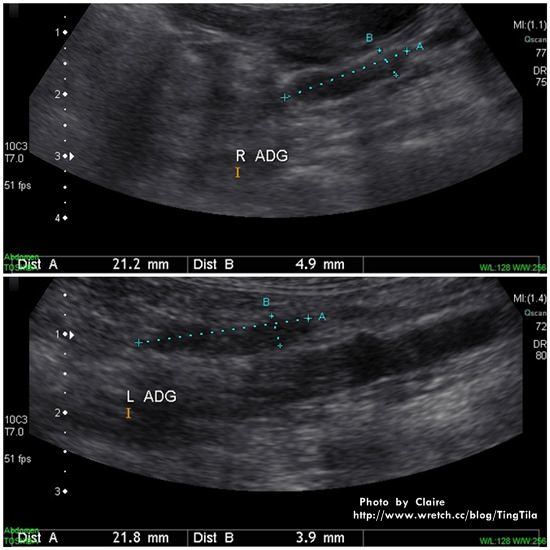

彩色腹腔超音波

超音波照出來黑的東西多代表是水、液體

一切看起來都是很正常!

需要注意觀察的地方為腎上腺

正常來說

左邊為0.41 cm (圖檔上單位為mm)

右邊為0.43 cm

而TILA

左邊為0.39 cm (正常範圍內,可接受)

右邊為0.49 cm

大於標準值,不過檢驗的數值都會有幾%的範圍內可接受

由喝水量和尿尿的次數下去觀察

尿尿量會不會很多,次數很頻繁

TILA現在都是吃鮮食,含水量很多~故排尿量也大

不過!! 如果吃鮮食之外~還另外喝很多水,就要注意了!!

杜普勒超音波可以看到血流的分布

腎臟大小正常

膽囊很乾淨~

膀胱也很清澈…空空如也!!都沒尿~哈